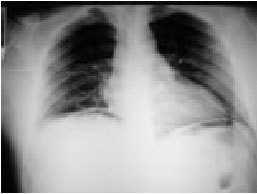

Figura 1. Radiografía de tórax: colección de gas con morfología de media luna en la región infradiafragmática derecha.

Caso clínico. Un varón de 38 años consultó por dolor súbito abdominal desde hacía 3 h. El dolor era continuo, localizado inicialmente en epigastrio e hipocondrio derecho y generalizado a todo el abdomen al cabo de 1 h. Se acompañaba de náuseas y vómitos. El paciente era fumador y 6 años antes fue diagnosticado mediante una endoscopia de úlcera péptica, pero no tomó fármacos antisecretores. En la exploración destacaba un aspecto de gravedad y signos de irritación peritoneal, pero estabilidad hemodinámica. Tanto la radiografía de abdomen en bipedestación como la de tórax evidenciaron una colección de gas con morfología de media luna en la región infradiafragmática derecha, que sugería neumoperitoneo (NP) (fig. 1). El paciente fue intervenido con urgencia, demostrándose una úlcera gástrica perforada, que requirió gastrectomía parcial. El postoperatorio cursó sin complicaciones.